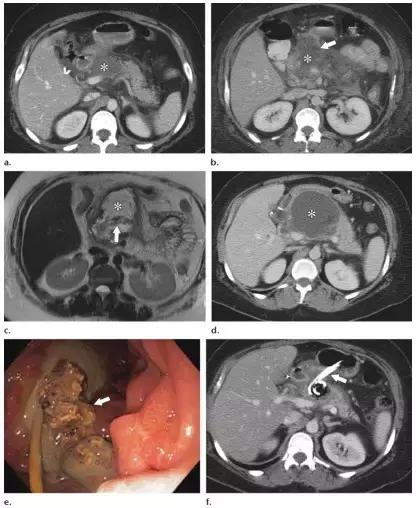

WON 可存在于胰腺实质,但更常见于胰周,也可同时累及胰腺和胰周(图 10)。有研究表明,对于病程超过 4 周胰腺炎,MR 的评估能力高于 CT。

MR 成像可以显示坏死物的数量,因此在制作手术计划时,MR 成像可作为增强 CT 的替代方法(图 11)。

图 11 发病 16 周的 47 岁男性坏死性胰腺炎患者。 a 轴位平扫 CT 图像示几乎累及整个胰腺的 WON(箭头),约有一半为液性密度。 b 随后轴位脂肪抑制 T2WI MR 图像示 WON(箭头)大部分为非液性坏死物和胰腺坏死,仅有少量液体信号。这样的病灶经皮或内镜引流效果差,需要创伤性更大的治疗方法